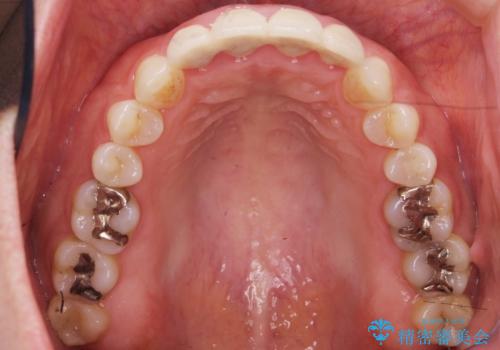

自然な仕上がりに大変喜んで頂けました。

単冠かつ適合の良いクラウンにより清掃性が良くなり、歯茎の腫れ・出血もなくなりました。

天然歯と見紛うほど自然なセラミッククラウンは、熟練した技工士さんの技術の賜物です。

クラウンの種類:ジルコニアオールセラミッククラウン エクセレント